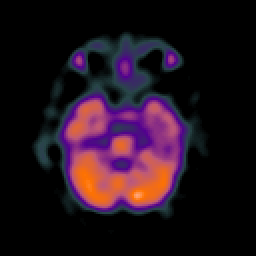

SPECT TC Study #4 -- Slice #18

[Home][Help][Clinical][Tour 1][Tour 2][Tour 3] Slice 18